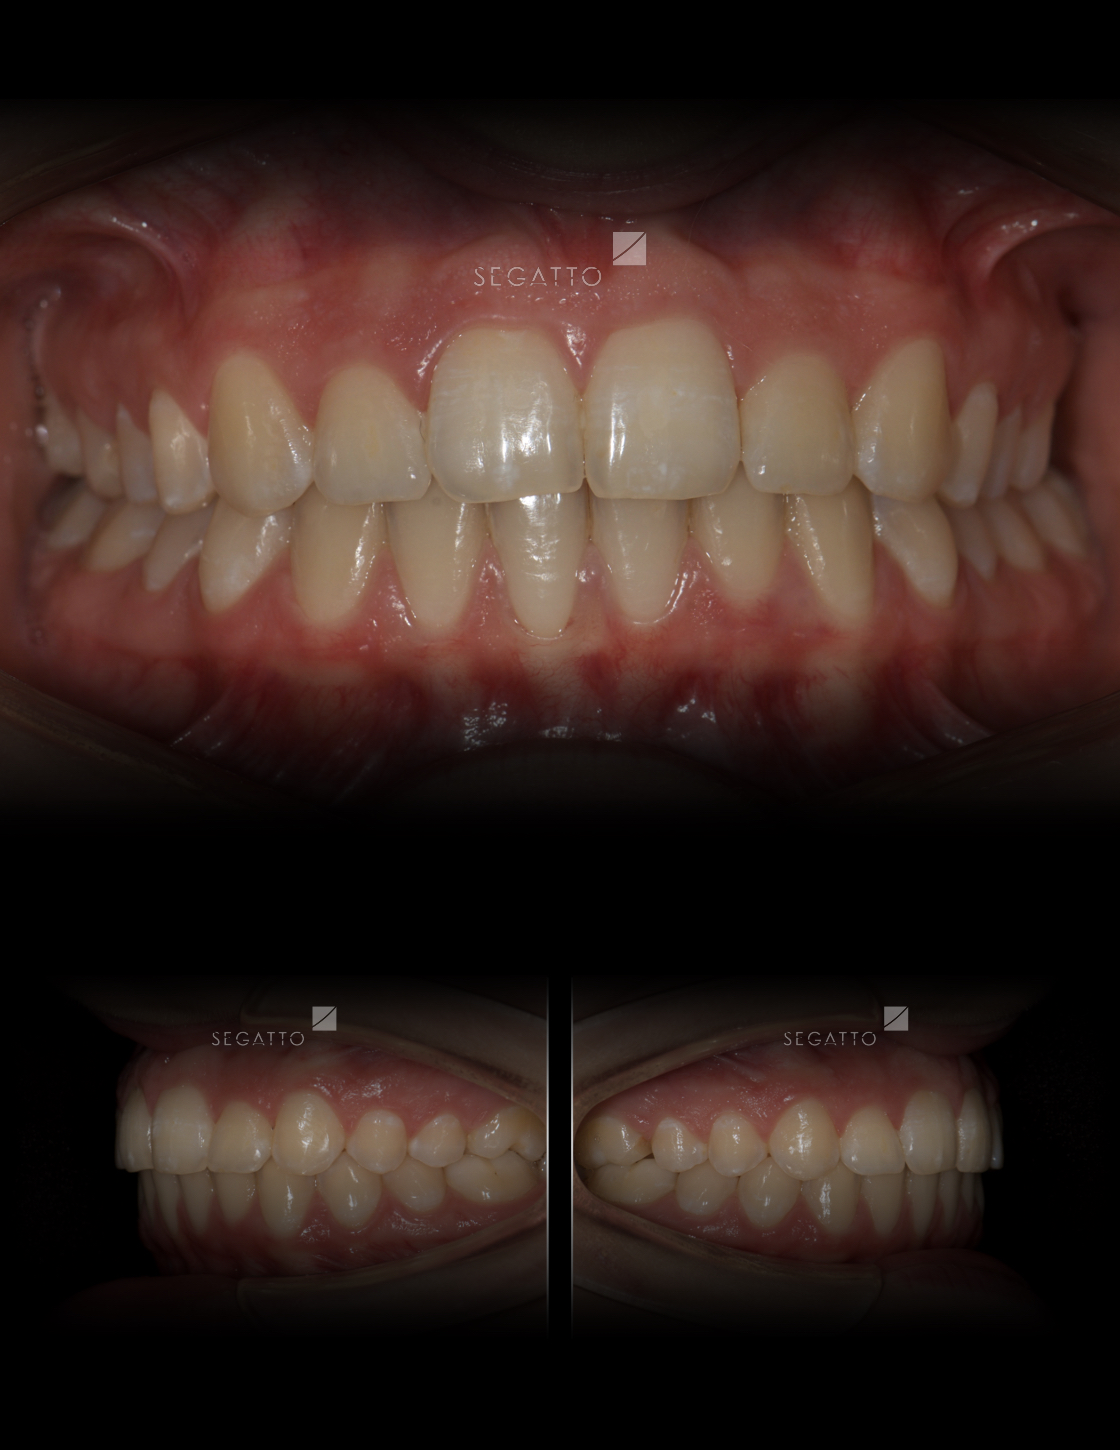

Orthodontics

Cases